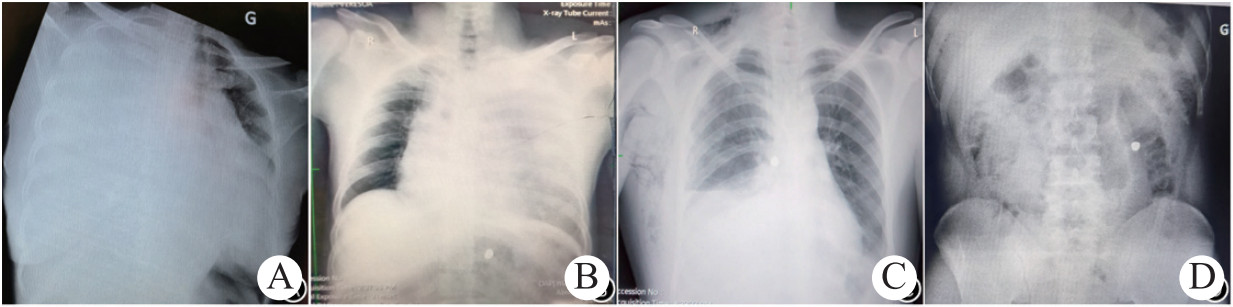

根据患者病史及查体诊断明确,11例患者均出现休克表现,且有不同程度呼吸困难和指脉氧饱和度降低;其中霰弹枪枪击7例,子弹在胸部体表的入出口小呈圆形(图 1A-B),步枪或手枪4例,子弹在胸部体表的入出口偏大呈条形(图 1C-D)。7例合并其他组织或器官损伤,6例胸部贯通伤。部分患者术前行胸部X线检查,病例3右侧胸部枪击贯通伤,胸部卧位X线示右侧大量胸腔积液,肺压缩,纵隔移位,心影大(图 2A);病例7胸腹联合枪击伤,子弹经左侧胸背部射入,滞留腹腔,胸部卧位X线示左侧大量胸腔积液,纵隔增宽,腹腔可见高密度影(图 2B);病例8胸部枪击穿透伤,子弹滞留胸腔,胸部立位X线示右侧胸腔积液,胸椎旁可见高密度影(图 2C);病例11胸腹部多发枪击伤,子弹滞留腹腔,腹部立位X线示左侧腹腔可见高密度影(图 2D)。

| A:病例3,右侧胸部枪击贯通伤,胸部卧位X线示右侧大量胸腔积液,肺压缩,纵隔左移,心影大;B:病例7,胸部卧位X线示左侧大量胸腔积液,纵隔增宽,腹腔可见高密度影;C:病例8,胸部立位X线示右侧胸腔积液,胸椎旁可见高密度影;D:病例11,腹部立位X线示左侧腹腔可见高密度影 图 2 部分患者胸腹部X线表现 |